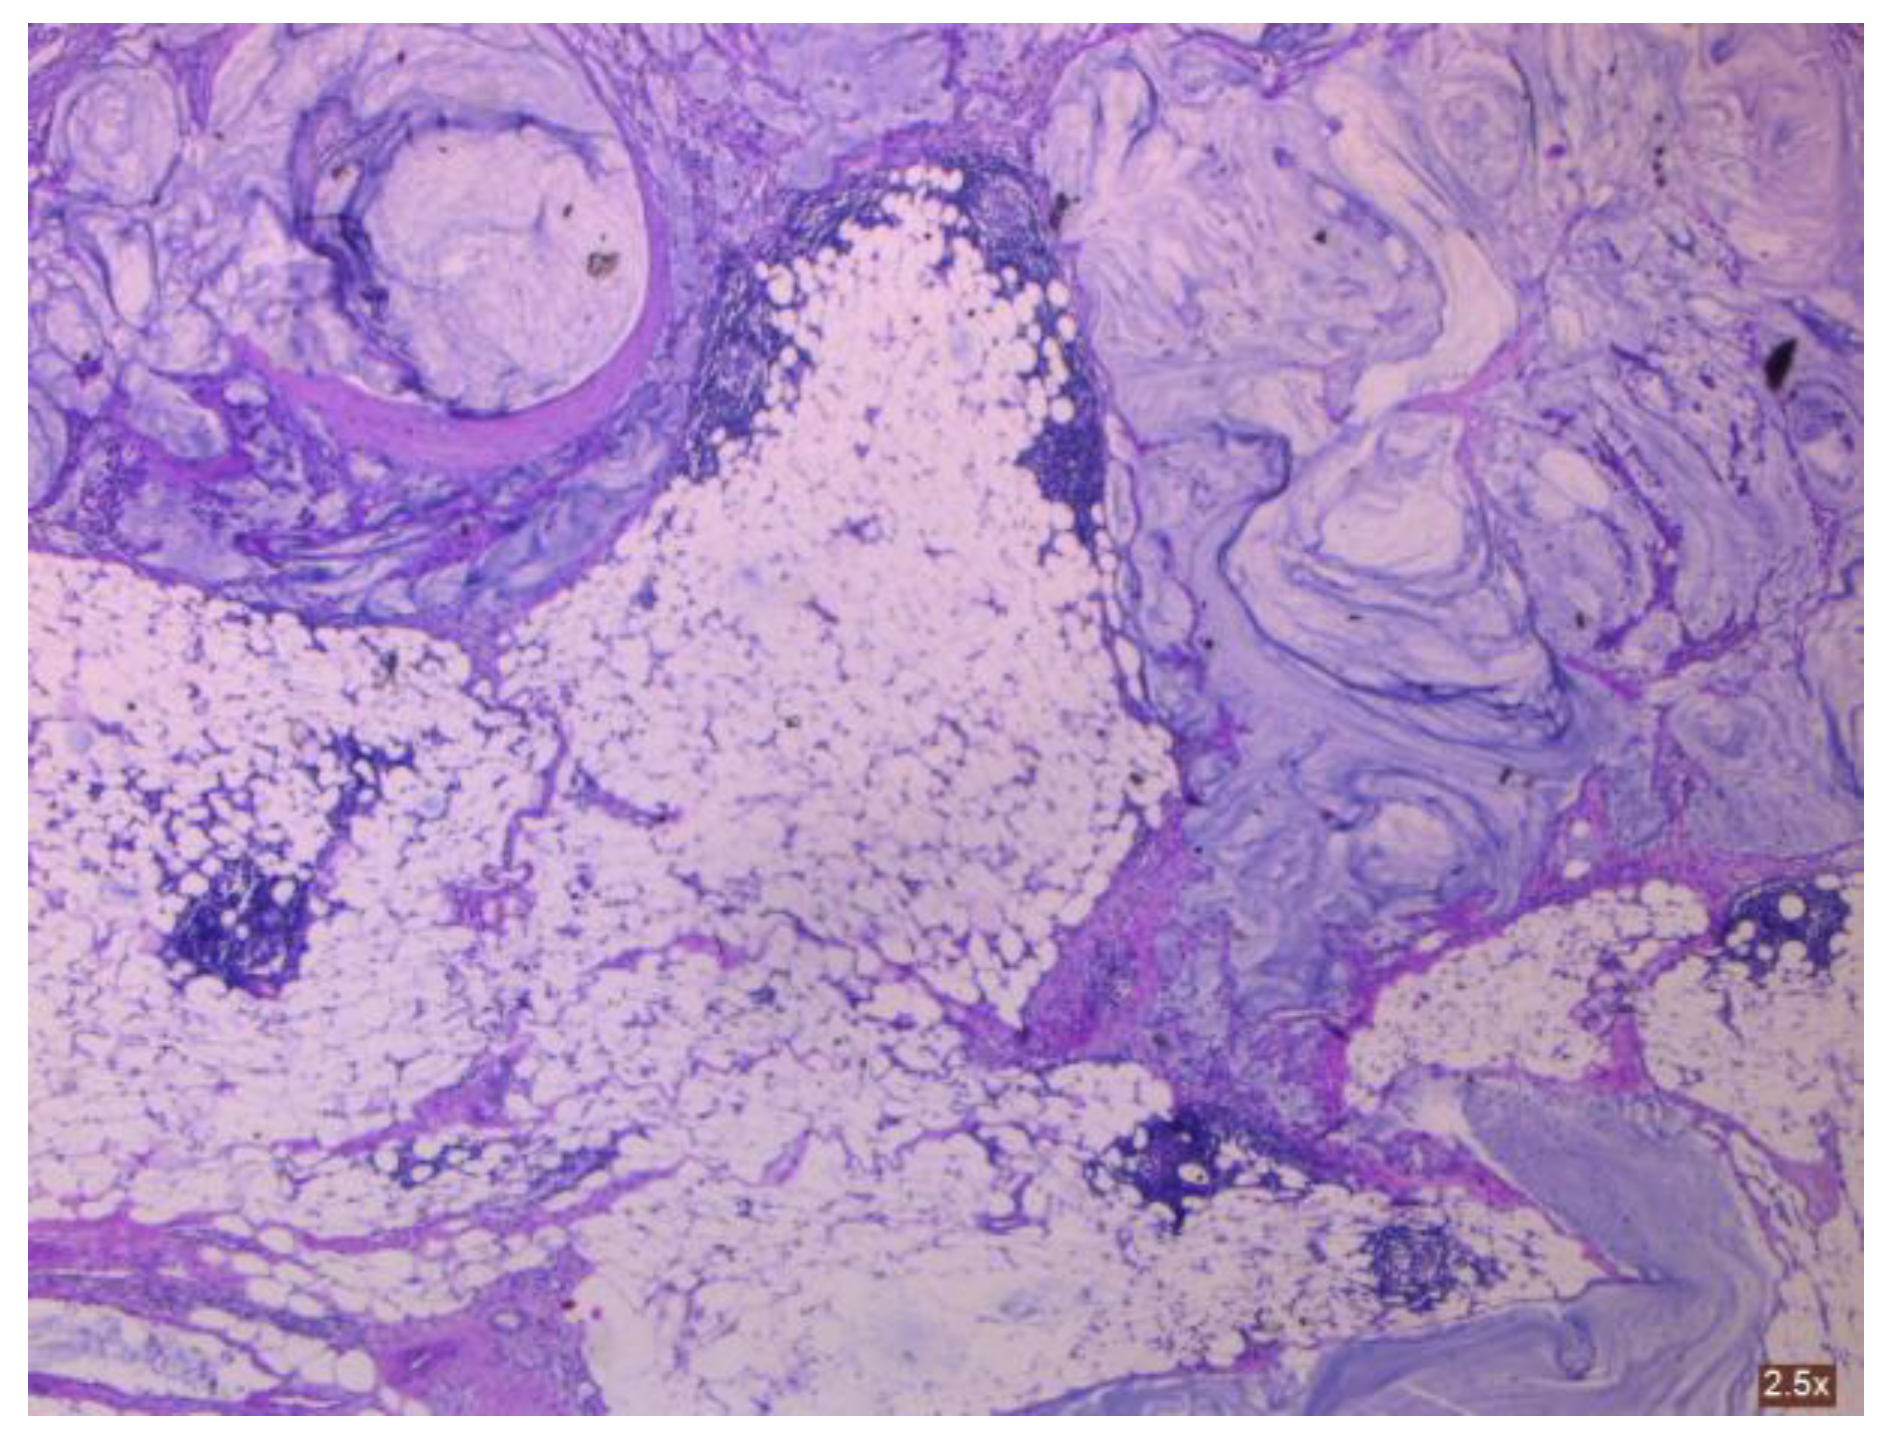

3.2.2. Clinical and Pathology Findings